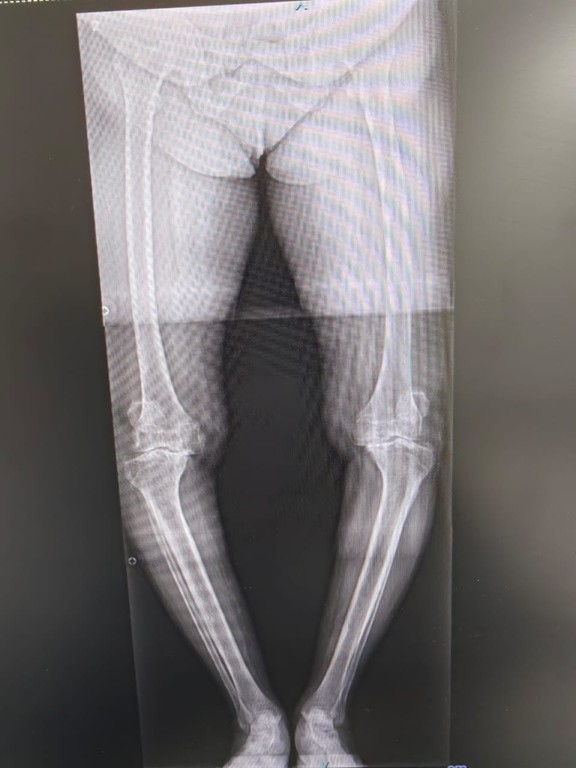

Severe osteoarthritis of both knee joints X-ray showing cartilage loss

Severe osteoarthritis of both knee joint

• X-rays to identify cartilage loss, reduced joint space, and bone changes